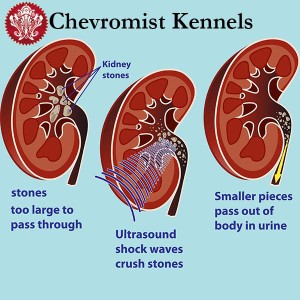

As Canine Hyperuricosuria is often an inherited condition, treatment is in the form of removing the stones from becoming a problem for the dog. The stones can be removed via surgery as well as by using sound waves (under ultrasonography) to break the stones into smaller pieces to allow them to pass through with the urine of the dog on their own.